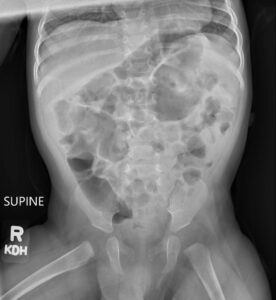

Incarcerated Gastric Volvulus and Splenic Herniation. Abdominal Radiograph Postoperative Day 33. JETem 2025